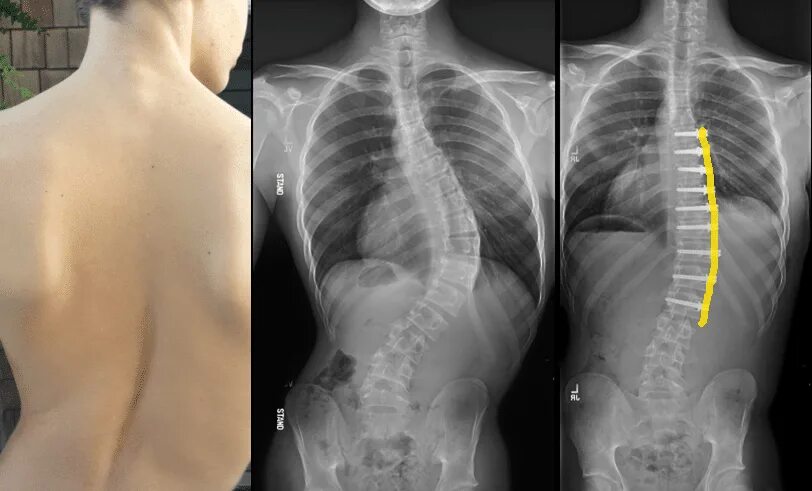

Сколиоз хирургия